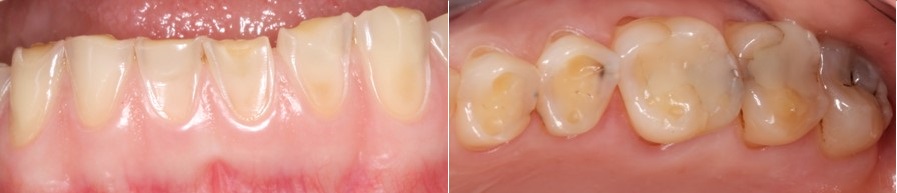

Σημαντική είναι και η φθορά στις μασητικές επιφάνειες των δοντιών που απεικονίζονται στις φωτογραφίες που ακολουθούν.

Όλα τα δόντια έχουν χάσει την μασητική μορφολογία τους, εκτός από την μεταλλοκεραμική γέφυρα στην κάτω γνάθο.

Τα σφραγίσματα και οι προσθετικές εργασίες δεν διαβρώνονται από τα οξέα και έτσι οι παλιές προσθετικές εργασίες ξεχωρίζουν στο στόμα, όπως φαίνεται χαρακτηριστικά στην φωτογραφία των δοντιών της κάτω γνάθου, δεξιά.